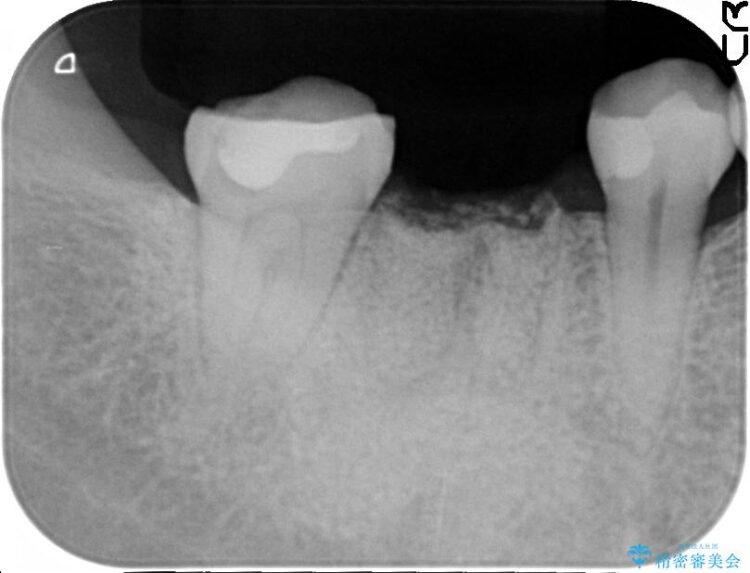

抜歯を行った当日に骨の維持をする為、人工の骨を充填しました。インプラントを埋入する際には、ほとんどが自分の骨に置き換わっており、頬舌的なへこみを引き起こす事もなく、審美性・機能性ともに維持する事が出来ました。

また今回の治療では「バイコンインプラント」を使用する事により、インプラントの土台とセラミッククラウンを付ける際にセメントが全く残らないという利点を生かしたところ、見た目にも綺麗に仕上がり、患者様にも喜んでいただきました。

※下あごのインプラント治療の場合、ネジで止めるインプラントでは「ネジ止め用の穴」が少し見えてしまい審美性に欠けるデメリットがあります